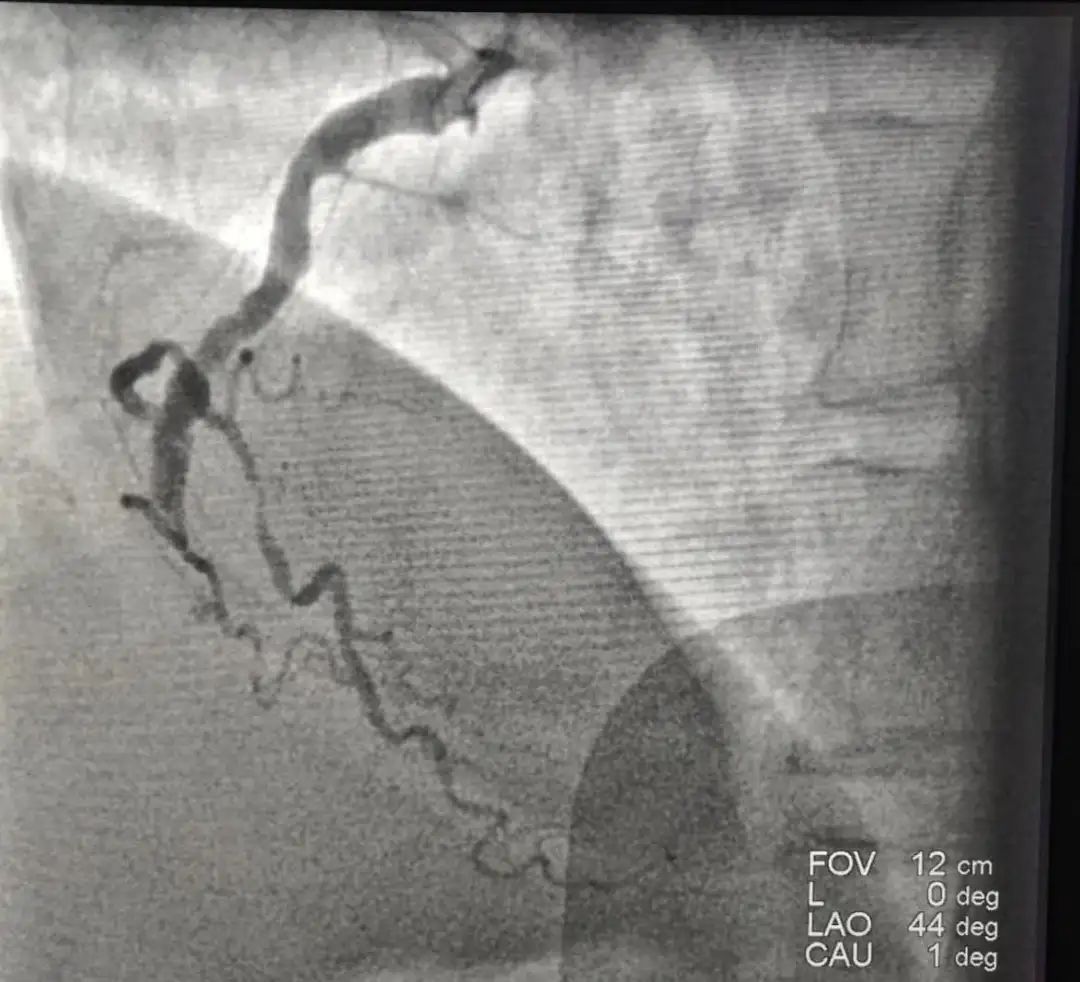

下午4点马先生被直接送至导管室,赶紧造影,发现右侧血管完全闭塞,左侧两个血管也有不同程度狭窄。我们第一时间打通血管,患者得到了救治,目前病情已经平稳。回到监护室,家属问我们,老马好好的,怎么就心梗了。老马不抽烟、没有糖尿病、饮食上也算注意,不太吃油腻的食物,偶尔还活动活动。有点高血压,但吃着药,我们平时每天还喝红酒来软化血管,怎么就心梗了?

术前